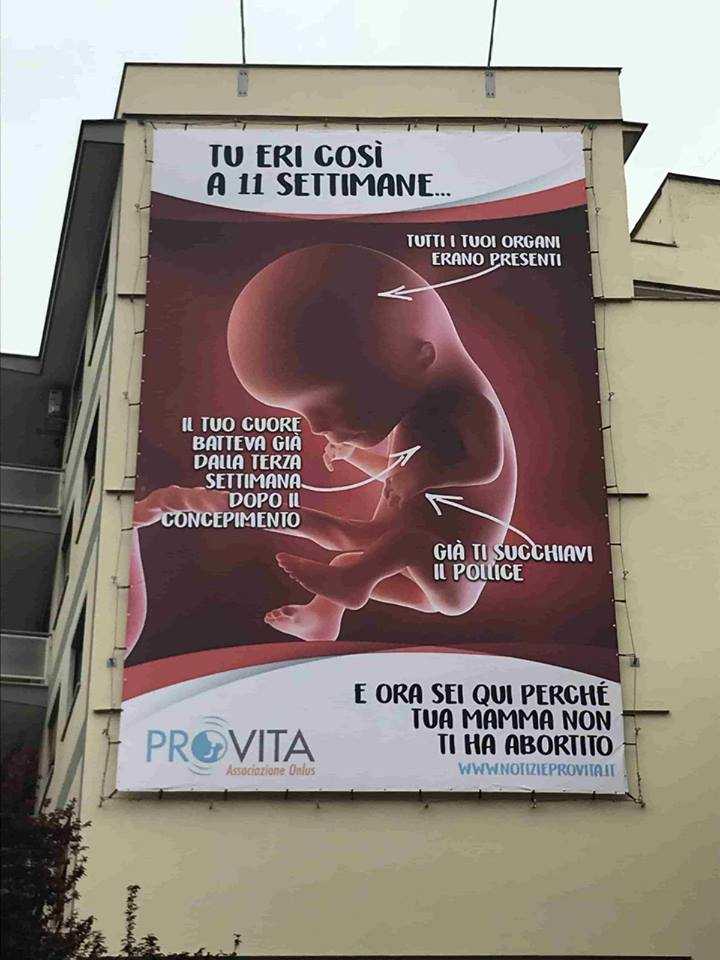

Cosa c’è di vero nel manifesto anti aborto di ProVita